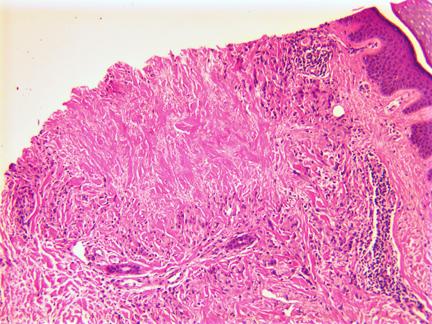

间质模式:特征为真皮中上层组织细胞嵌入嗜碱性黏蛋白并浸润于胶原束间。胶原纤维出现不完全变性。

图:左下部和左上部区域的 2 个不完全胶原变性区域,中间有大面积的正常真皮胶原(间质或不完全环状肉芽肿)。(HE染色 100x)

穿通型GA:表现为栅栏样淋巴组织细胞肉芽肿包绕的黏液样变性胶原纤维经表皮排出。

图:坏死肉芽肿位于真皮上部,在右侧可以看到无细胞物质刺穿表皮(HE 100x).